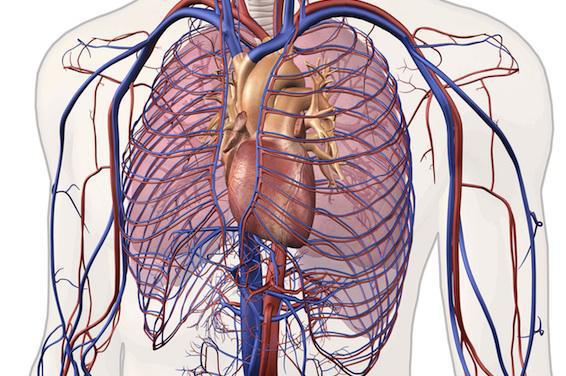

Initialement, ce poumon artificiel a été imaginé pour traiter les patients atteints d’hypertension pulmonaire (une maladie vasculaire qui affecte les vaisseaux des poumons) et qui ne peuvent pas bénéficier d’une transplantation. Chez ces patients, la partie droite du cœur qui envoie le sang vers les poumons n'est plus assez puissante, entraînant une oxygénation du sang de moins en moins bonne.

Sur le même mécanisme qu’une dialyse rénale, ce poumon portatif permettra de remplacer l’activité des poumons. « Une petite canule placée dans une veine au niveau du cou ira jusque dans la partie droite du cœur pour faire passer le sang dans la machine afin de l’oxygéner et d’éliminer le dioxyde de carbone. Puis, le sang sera réinjecté dans la partie gauche pour être distribué aux organes », détaille le chirurgien.